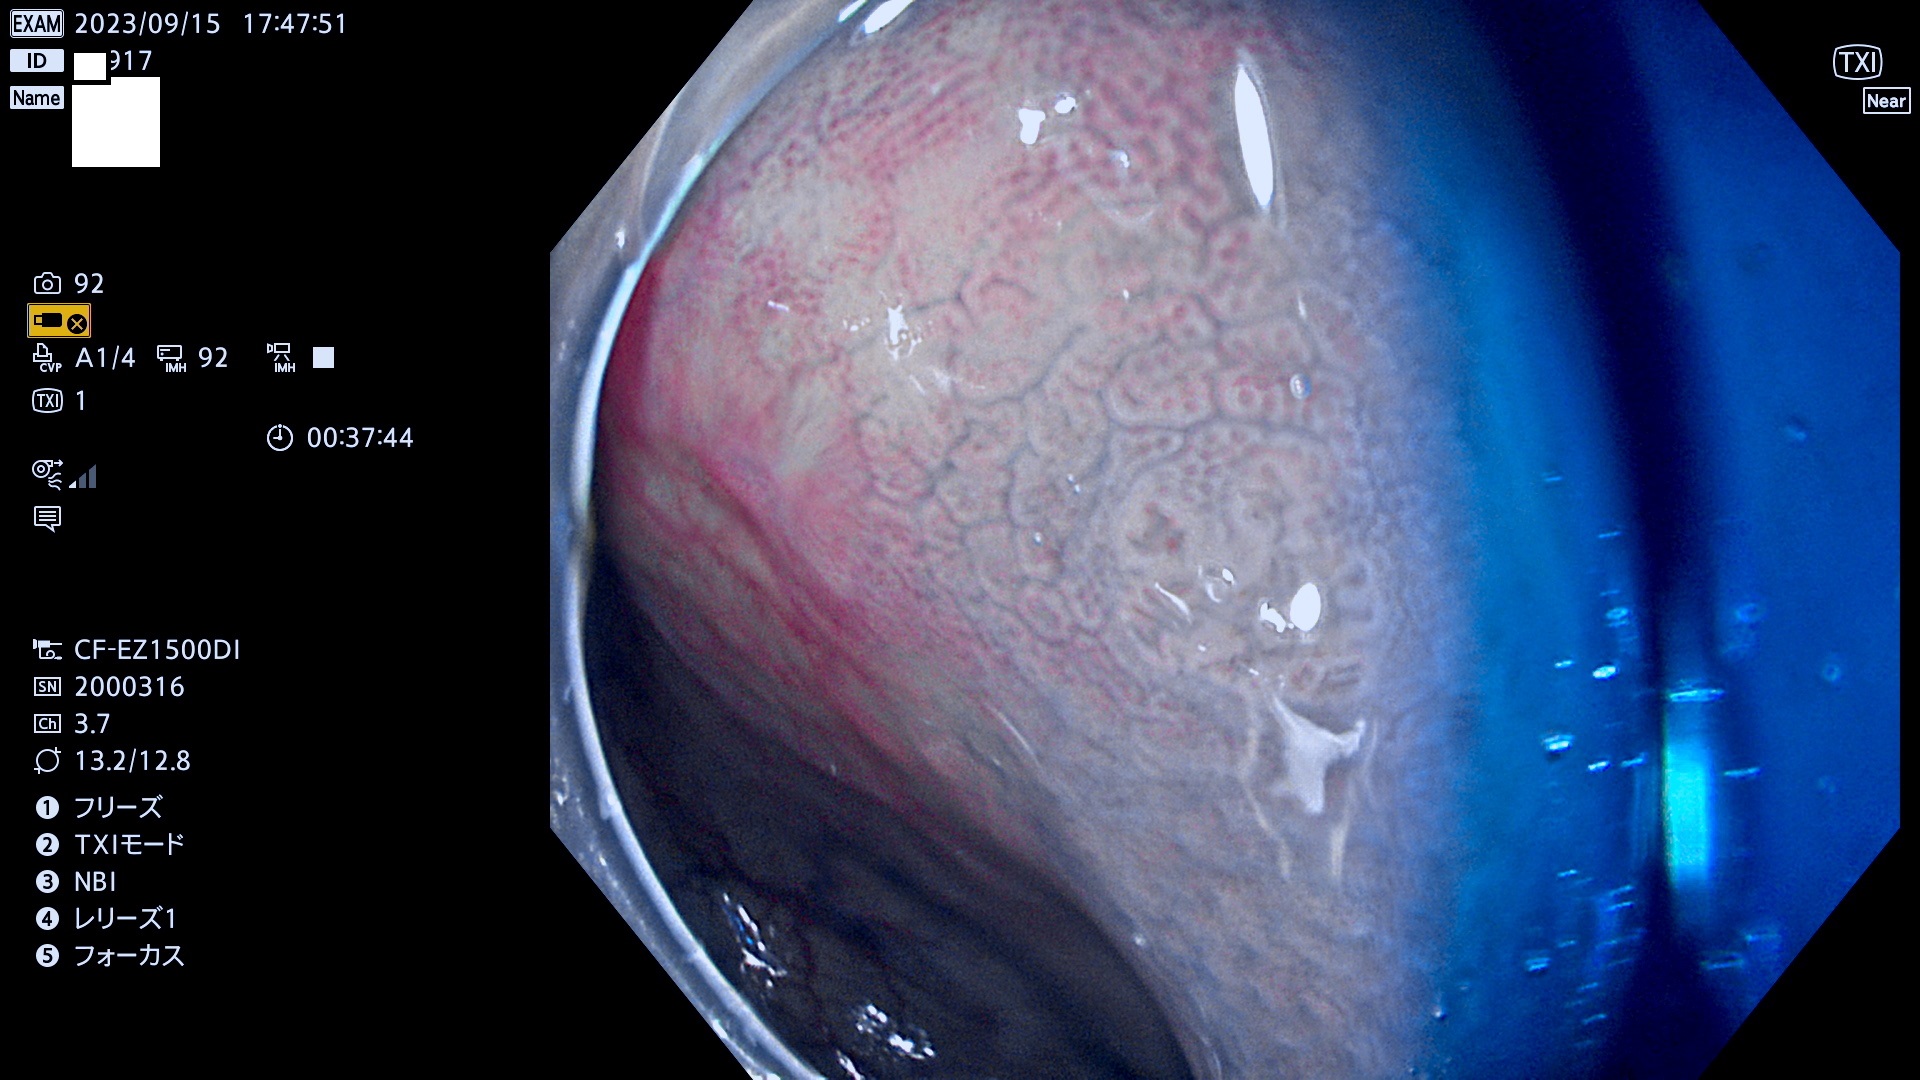

今週のUb、Uc型腺腫

表面型腺腫(Flat Adenoma)の中で、完全に平坦な物をUb、陥凹している物をUcと呼びます。平坦隆起型(Ua)よりも、発見が難しく危険な病変です。このタイプは「内視鏡後・大腸癌の重要犯人」であり、この発見率は「腺腫発見率」よりも、重要な意味があります。

毎週の検査(木・金・土・日)に発見されたUb、Uc型・腺腫を、その週の日曜の夜にUPし1週間、提示します。

抽出の対象期間 2023年9月14日(木)〜9月17(日)の4日間(48件の検査)7件